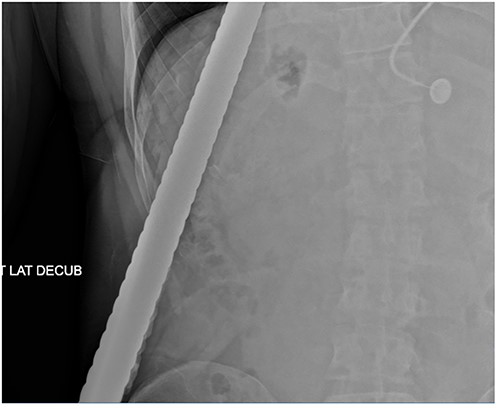

A 43-year-old male patient presented to the emergency department after falling onto an exposed rebar at work at a construction site. The rebar entered the patient’s left flank and exited via the anterior aspect of the left chest. His initial blood pressure was 137/96 and his heart rate was 114 beats per minute. Physical examination revealed a rebar measuring ~80 cm impaled through the patient’s left flank and left chest (Fig. 1). While in the trauma bay, an abdominal X-ray was obtained, demonstrating a right-sided pneumothorax, and the rebar’s path was extending into the left anterior thoracic cavity (Fig. 2). Afterward, the patient was taken to the operating room where a left thoracotomy and exploratory laparotomy were performed.

Rebar penetrating through the left flank through the left anterior chest.

Abdominal X-ray demonstrating the rebar trajectory into the left anterior chest; the path is distorted secondary to patient positioning during imaging.